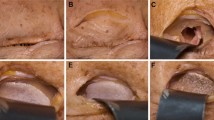

A total of 11 fresh frozen cadaver heads, each providing one left and one right intact orbit, were included in the study. The orbital floor was exposed via an intraoral approach (Fig. 1a). Standardized isolated orbital floor defects were symmetrically created by piezosurgical removal of the orbital floor (Fig. 1b). The posterior ledge, corresponding to the dorsal tip of the orbit, and the inferior-medial strut, as a bony connection between the medial and caudal orbital walls, were preserved. The bulbus was inflated with 0.9% NaCl to 30 g, corresponding to the weight of the orbital contents [21, 23, 24], to simulate orbital tissue herniation into the maxillary sinus. The fractures were exposed via an infraorbital approach, and repositioning of the herniated orbital tissue was performed with a periosteal elevator. PDS foils (Ethicon, Norderstedt, Germany) with 0.25 mm (ZX3) or 0.50 mm (ZX4) thicknesses were placed on the intact bony buttresses into the fractured orbits (Fig. 1c).